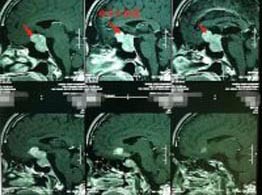

56岁的张先生,3天前出现间歇性头晕,伴有夜间尿多,当地医院就诊,头颅CT检查发现有颅内占位。广东三九脑科医院头颅MRI示:鞍区巨大垂体腺瘤伴瘤卒中,大小约4.3cm×3.1cm×2.8cm,邻近双侧颈内动脉及双侧大脑前动脉受压移位,右侧颈内动脉部分被包绕,视交叉明显受压上抬并向前移位。头颅CTA示大脑前交通囊状动脉瘤,大小约4.6mm×3.4mm。

▲术前MR ▲术前DSA